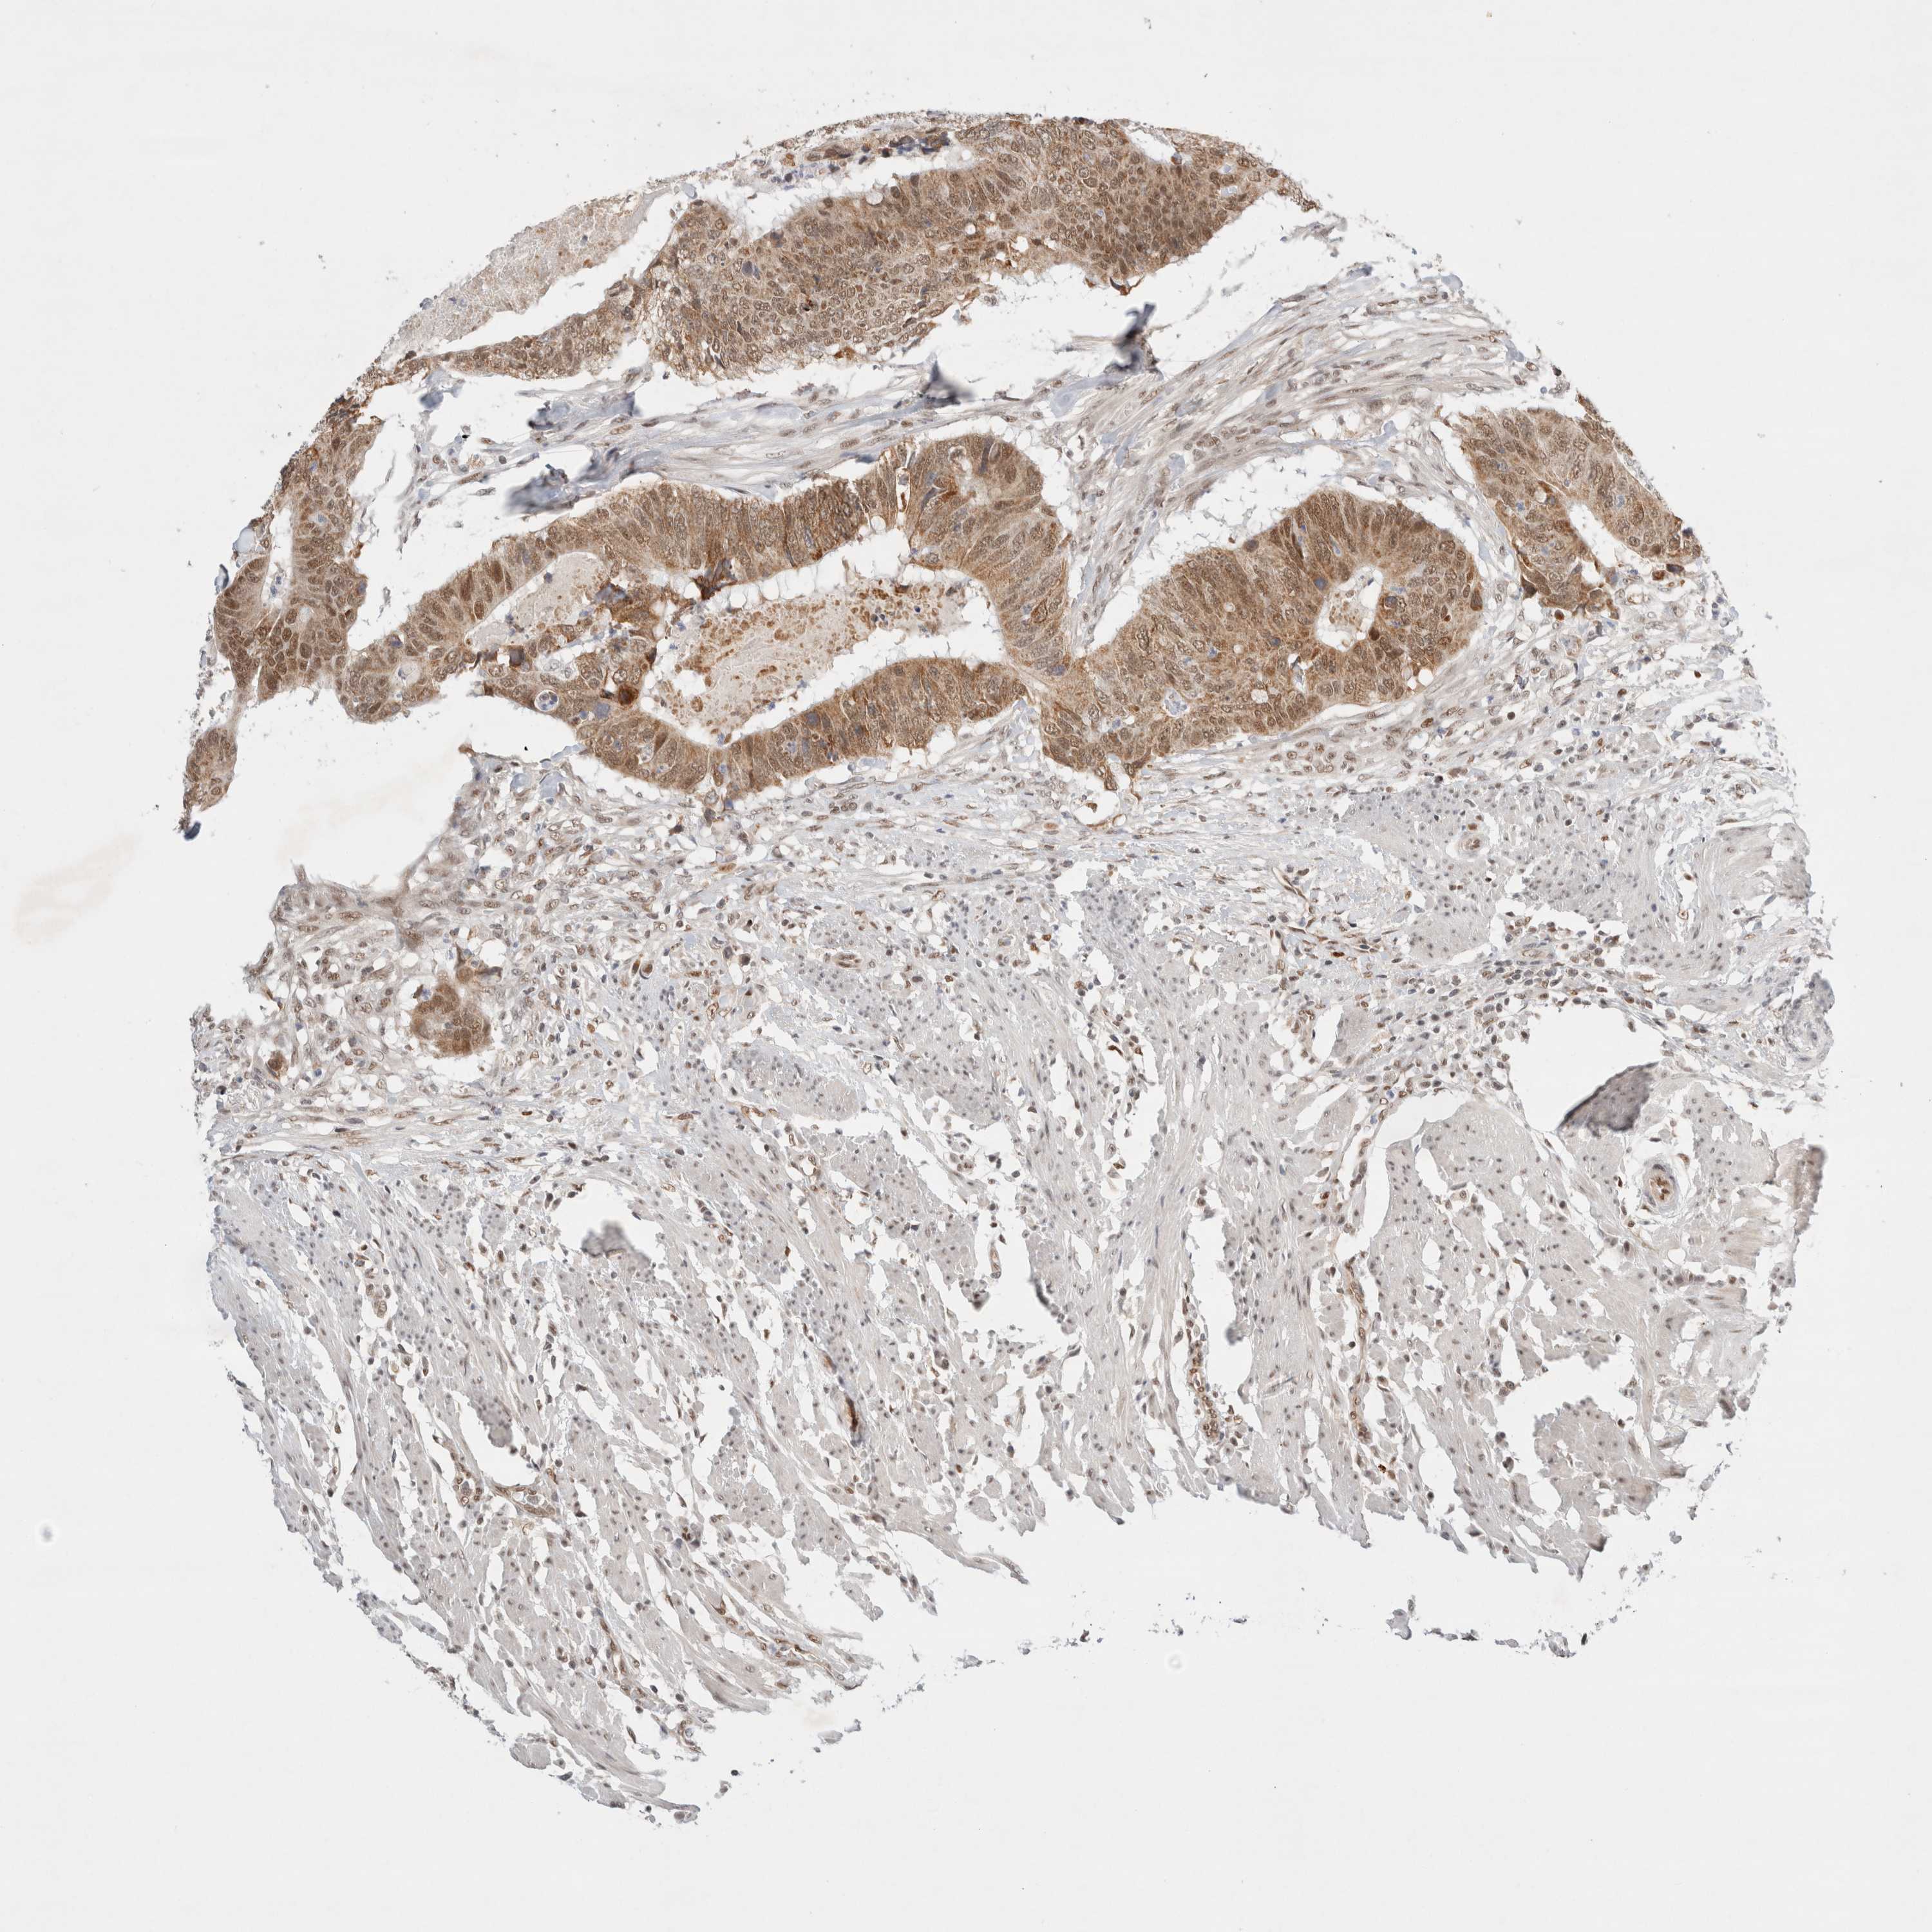

CANCER COLORECTAL CANCER Show tissue menu

Colorectal cancer

Human cancer

Colon adenocarcinoma